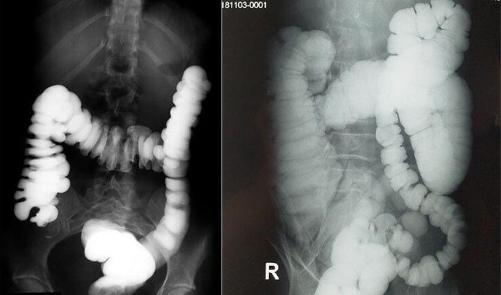

▲ 图6

大肠钡剂灌肠造影 了解大肠的长度和形态